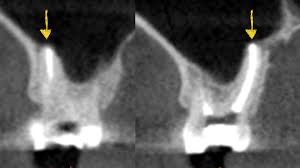

拔牙後3-4個月大多數患者均已完成癒合,但仍有極少數案例仍未達100%癒合的情況,本人以自身經驗以下圖進行解說(為極少數案例特別紀錄):

絕大部分患者在拔牙3-4個月後均已經是骨癒合情形,因爲是常見情況,故本人不會進行記錄。(我只會記錄罕見情況。)

以下圖為例,一般拔完牙後均等待數個月牙肉及齒槽骨癒合後,再進行植牙評估與植牙、補骨手術。(除非是少數齒槽骨條件極差的情況,需重建後才能植牙!)